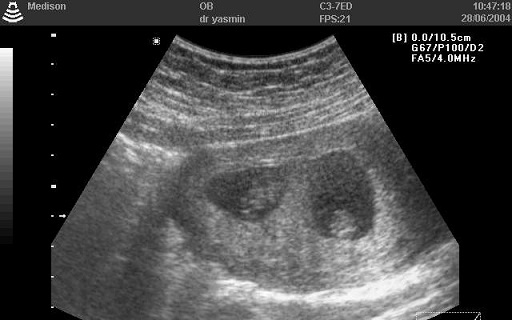

Elviselhetetlen hátfájásra panaszkodott kétórás edzése után egy amerikai futónő, aki épp a félmaratoni táv teljesítésére készült. Kiderült, hogy fájdalmainak oka nem sérülés, hanem terhesség: az edzés másnapján, június 3-án újszülöttet tarthatott a karjában.

A kórházi vizsgálaton férjével együtt meglepődtek, amikor az orvosok magzati szívhangot találtak. Az anyát azonnal a szülőszobába szállították, ahol kislánynak adott életet. Az orvosok szerint a baba a várhatónál öt héttel korábban született, 2900 grammos súllyal és 48 centiméterrel.